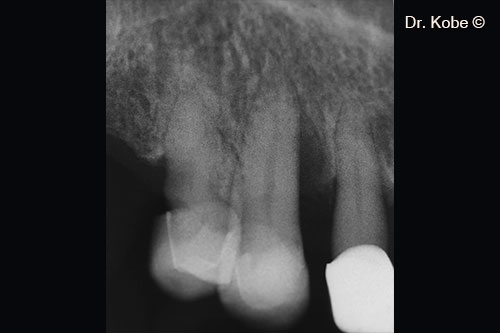

Vertical bone defect on the radiograph